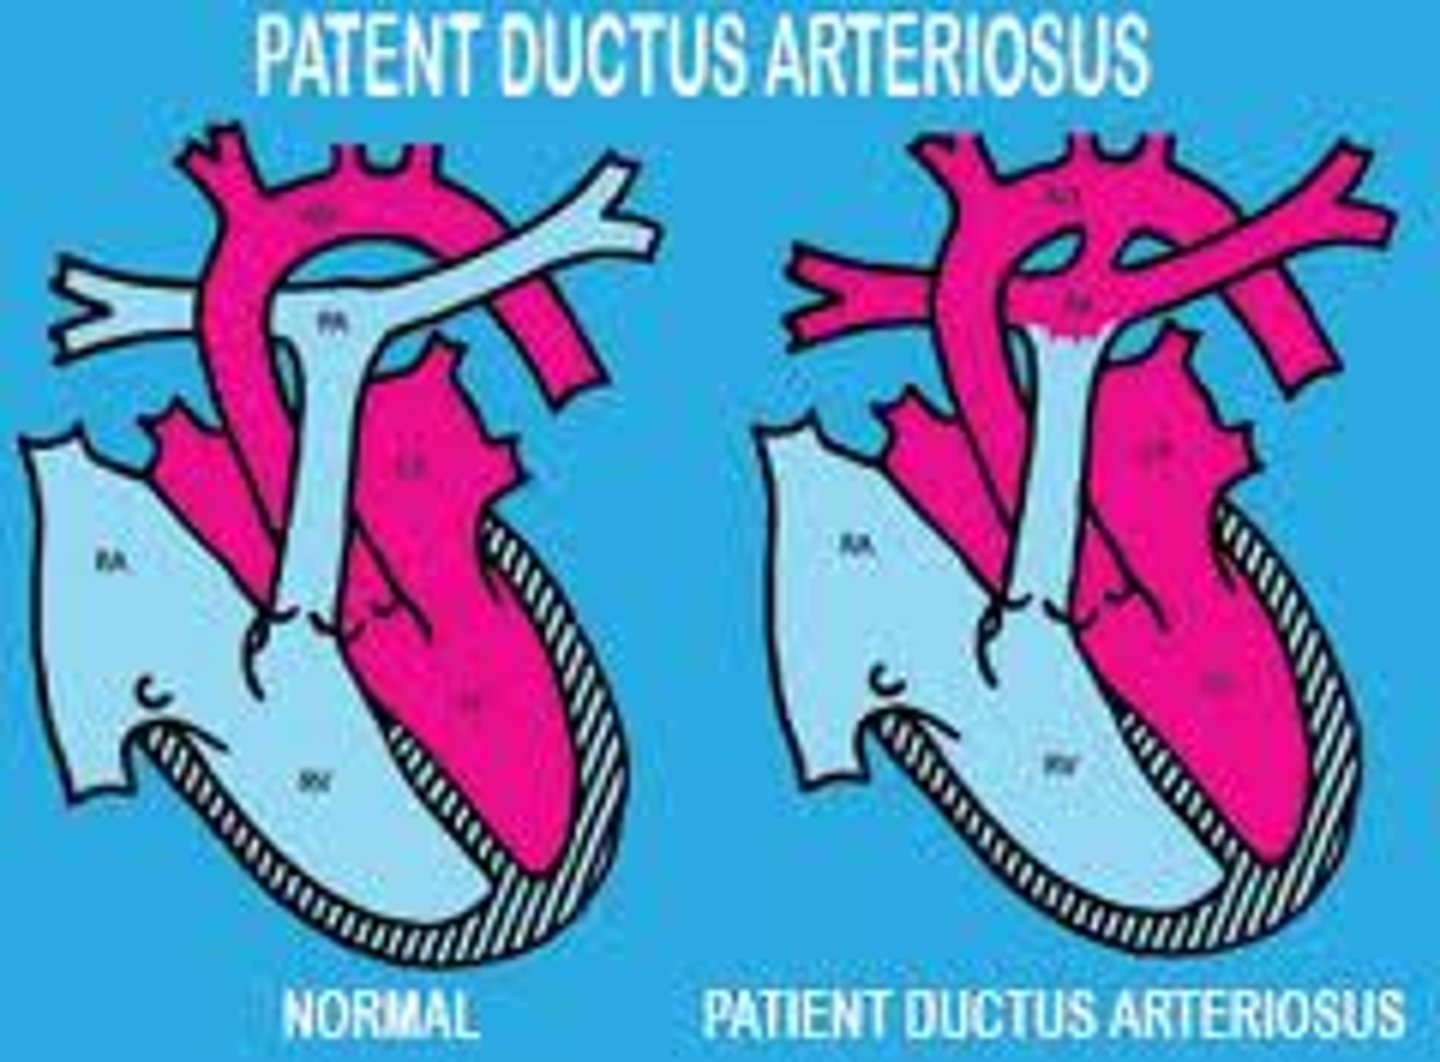

Continuous "machine-like"heart murmur

PDA (close with indomethacin; open or maintain with PGE analogs)

Congenital Rubella

Late cyanosis in lower extremity

failure of branchial arch 6